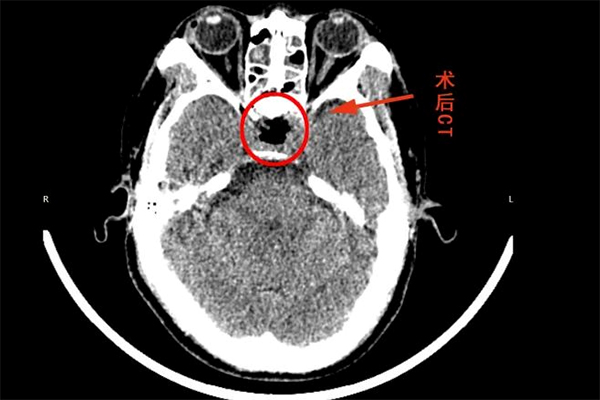

▲ 術后頭部CT

謝宏剛主任針對患者病情進行了詳細分析,認為垂體腫瘤位置深,臨近視神經(jīng)、海綿竇等重要結(jié)構(gòu),手術風險和難度比較大,預先與團隊分析了術中可能存在的風險及處理方案,在做好了充分的準備后,歷時4小時,成功為患者進行手術,術后復查CT手術效果滿意,不日即可出院。